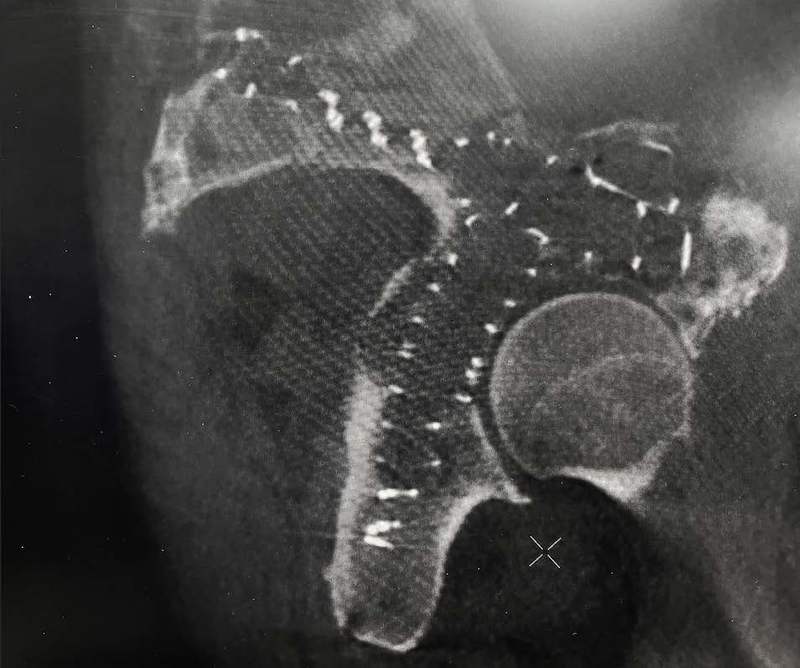

The 63-year-old patient presented with a pathologic acetabulum/hemi-pelvic fracture, and osteolysis with uncontained defect from metastatic lung cancer and additional co-morbidities. The patient has been treated with radiation for metastatic bone disease of the pelvis, and was bed ridden living in a skilled nursing facility due to severe pain and dysfunction resulting from his pathologic pelvis fractures. The patient was brought to surgery and IlluminOss implants were inserted percutaneously through the posterior column, anterior column and LC2 to provide fill and stability for the uncontained osteolytic defect. The implants were filled with a photodynamic liquid monomer and cured with visible blue light. At post-op day 1, the patient was weight bearing as tolerated using a walker. The patient was discharged back to the SNF on post operative day 1 and then from the SNF to home at 2 weeks post procedure. At 6 weeks follow up, patient uses the walker in the community and ambulates unassisted intermittently at home.